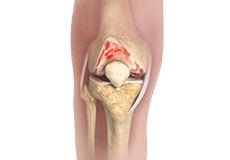

Osteoarthritis also called degenerative joint disease, is the most common form of arthritis. It occurs most often in older people. This disease affects the tissue covering the ends of bones in a joint (cartilage).In a person with osteoarthritis, the cartilage becomes damaged and worn out causing pain, swelling, stiffness and restricted movement in the affected joint.

Osteochondritis Dissecans of the Knee

Osteochondritis dissecans is a joint condition in which a piece of cartilage, along with a thin layer of the bone separates from the end of the bone because of inadequate blood supply. The separated fragments are sometimes called “joint mice”. These fragments may be localized or may detach and fall into the joint space, causing pain and joint instability.

Osteonecrosis of the Knee

Osteonecrosis is a condition in which the death of a section of bone occurs because of lack of blood supply to it. It is one of the most common causes of knee pain in older women. Women over 60 years of age are commonly affected, three times more often than men.